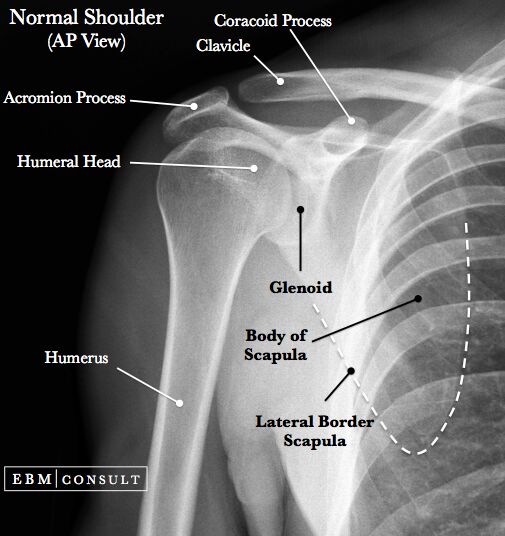

先看正常的

↑正常的shoulder X-ray AP view(前後方向 X 光),glenoid與肱骨頭會有一定的重疊,無empty